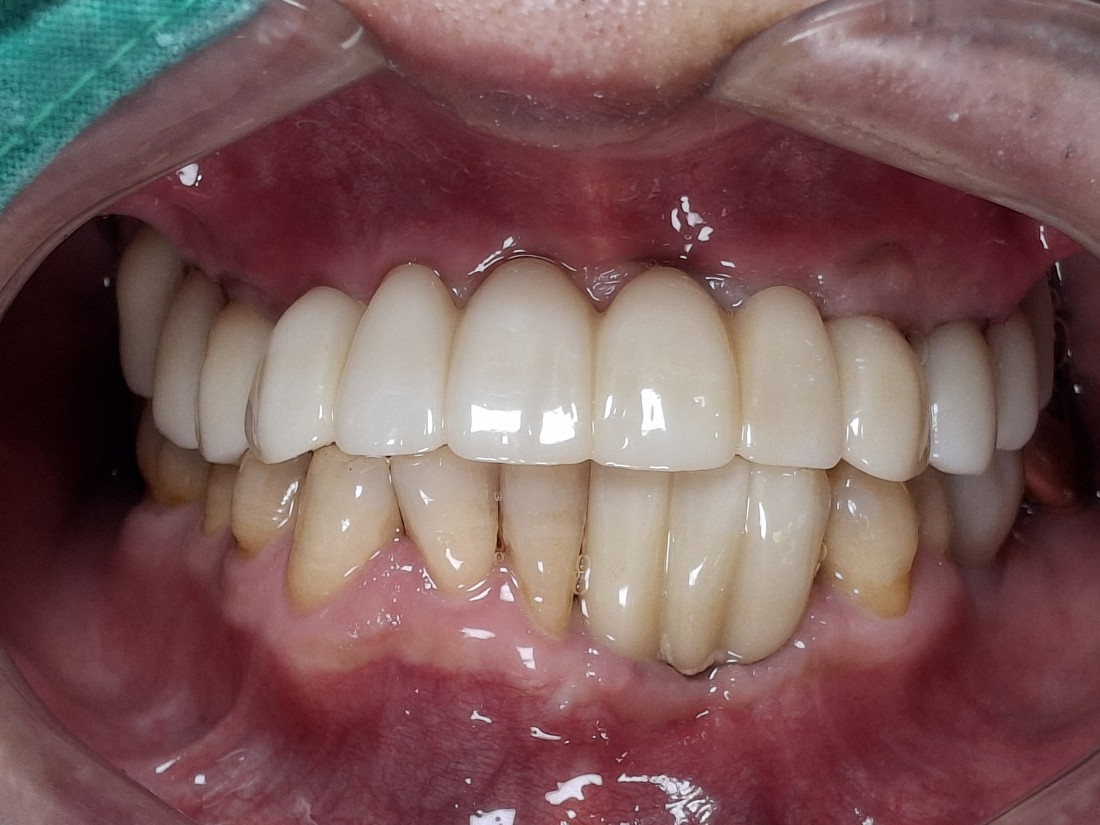

전남광주 임플란트 치과에서는

디지털가이드 임플란트 수술방법으로

한 번에 8개 이상의 임플란트를

심을 수 있습니다.

위, 아래 전체 임플란트를

단 두 번의 수술만으로 완성할 수 있어

임플란트 치과에 자주 내원하지 않으셔도 되고,

붓기 / 출혈 / 통증도 적기 때문에

빠른 회복을 기대할 수 있습니다.